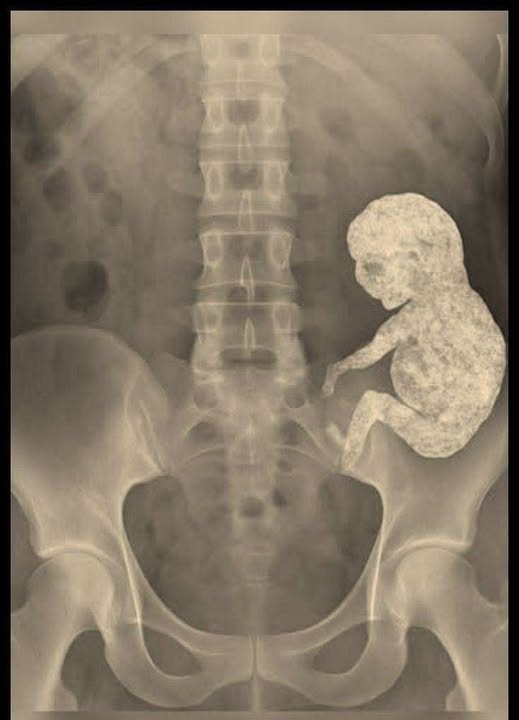

Une forme apparut sur l’écran. Recroquevillée comme un bébé dans le ventre de sa mère. Une masse dense et minéralisée. Un lithopédion. « Un enfant de pierre », dit le chirurgien. Et il se tut, comme si les mots avaient perdu leur sens.

Quand, des années plus tard, elle accepta enfin l’opération, les chirurgiens se préparèrent à l’extraction, comme pour lui dire adieu. Un silence de mort régnait dans la salle d’opération. Après l’opération, l’un des médecins admit que, pour la première fois de sa vie, il éprouvait de la compassion pour « l’objet extrait ». Il avait quelque chose d’humain en lui : une forme, un symbole, une signification.

Rosa se réveilla dans une chambre d’hôpital et demanda à voir ce qu’elle avait porté en elle pendant trente ans. Une petite masse grisâtre et irrégulière, comme une figurine de marbre. Elle la caressa du bout des doigts et dit : « C’est encore chaud. »